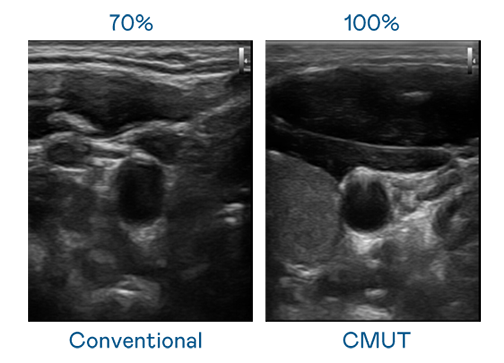

CMUT 技术是一种用电容式微机电元件来产生超音波讯号的技术。与传统 PZT 压电式技术相比,CMUT 频宽增加 30%,更宽频的超音波讯号让影像解析度大幅提升,是实现高影像品质医疗超音波扫描、促进精准医疗发展的关键技术。

超音波影像的解析度高低,首先取决于探头能发出的讯号频宽。AG亚游 CMUT 可提供高清晰的超音波讯号,提供高频宽、高灵敏度、影像纹理细节更高的超音波影像,协助医护人员缩短影像判读时间及利用精准的医疗影像进行诊断。